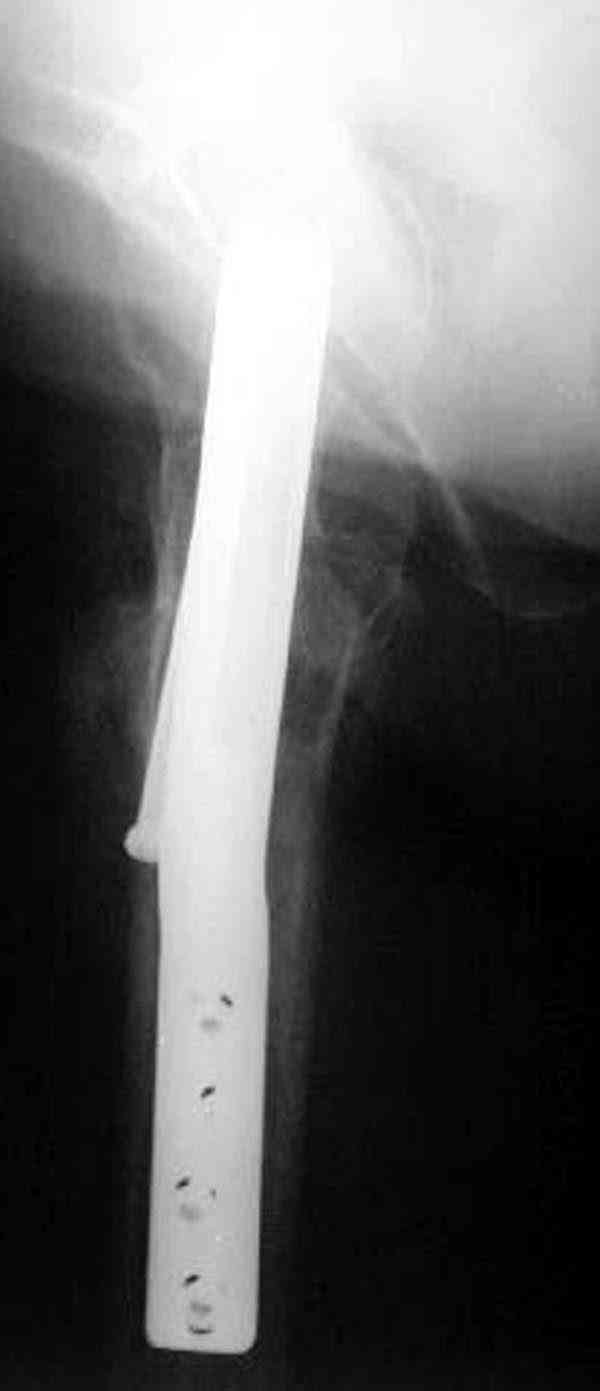

Коллега Челноков прав, здесь еще имеется риск перелома за счет ослабления латерального кортекса. Во время установки канюлированных шурупов за редким исключением спица вводится с одного раза, множественные попытки ослабляют латеральный кортекс, что станет источником перелома в этом месте.

Здесь случай перелома из-за ослабления латерального кортекса через 3 недели после операции на шейке. Шурупы были установлены под большим углом, слабый латеральный кортекс не выдержал нагрузку.